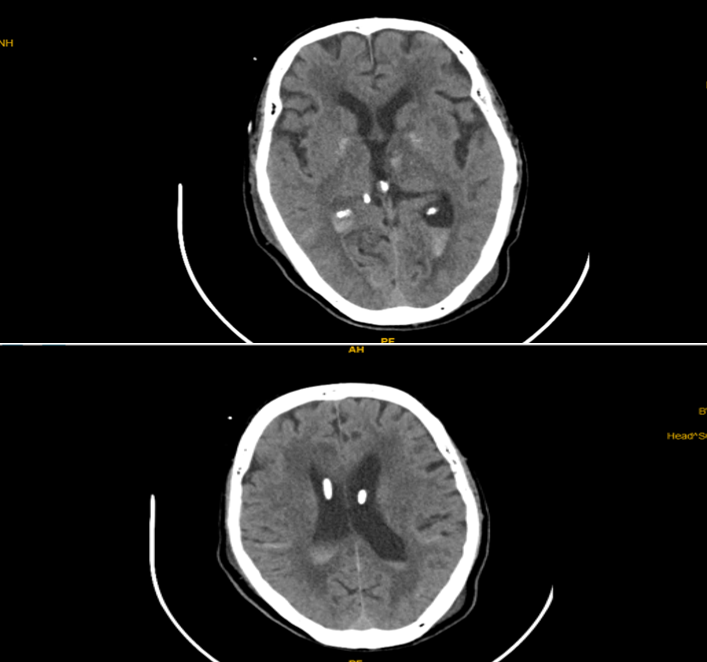

Bệnh nhân xuất huyết não thất được đặt EVD và bơm tiêu sợi huyết

CT sọ não sau bơm 3 liều Alteplase